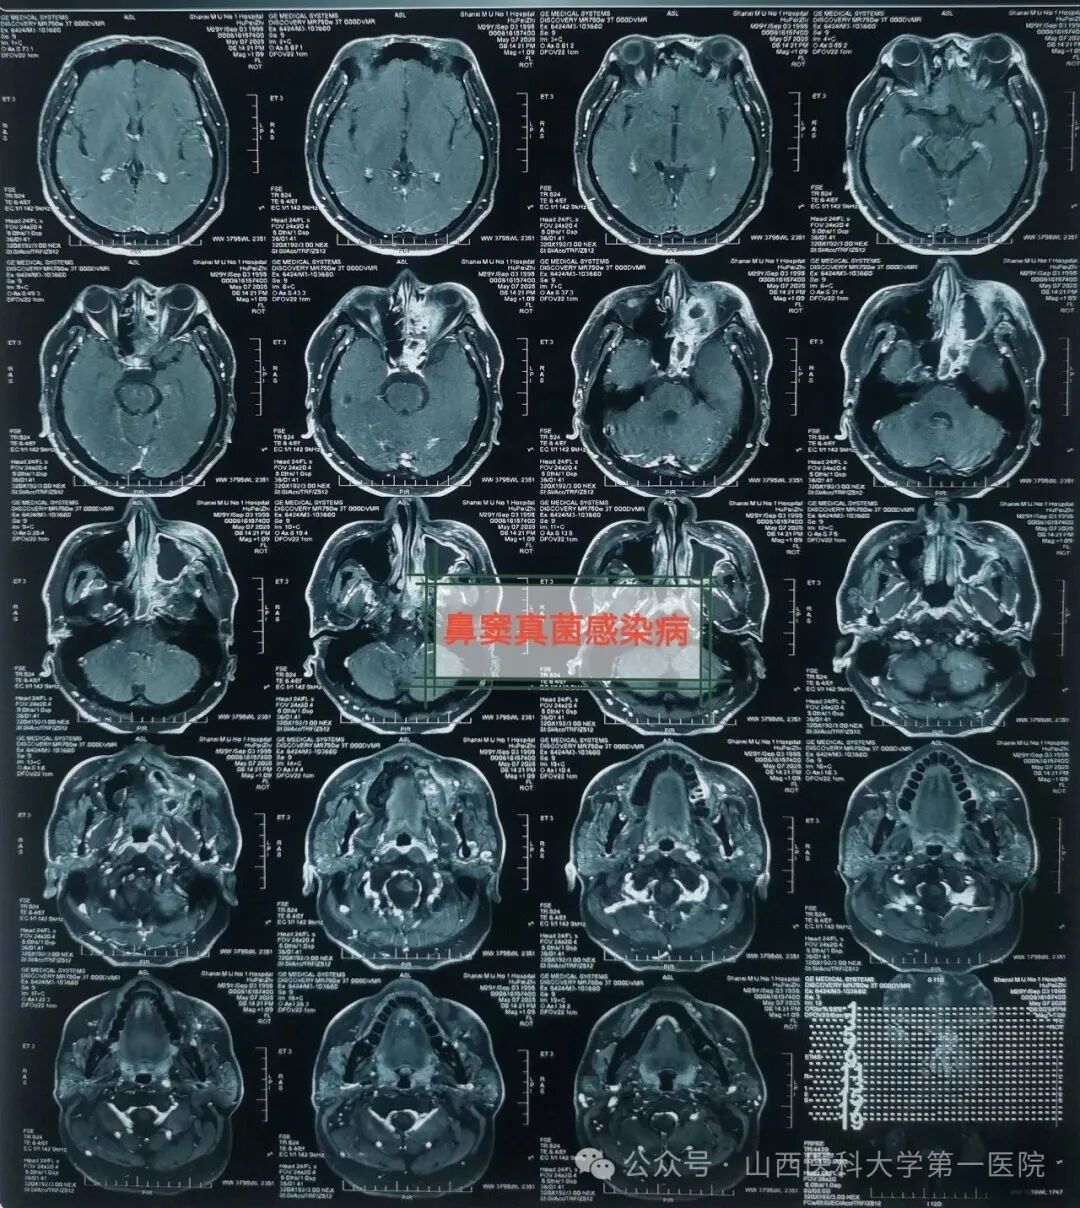

49岁的袁先生过敏性鼻炎多年,合并糖尿病与痛风,一直药物维持治疗;2年前因合并鼻窦炎,口服药物治疗效果不佳;近数月以来病情逐渐加重,鼻塞流涕,最近头痛头闷症状越来越严重同时出现鼻涕带血丝,就诊于山西医科大学第一医院耳鼻咽喉-头颈外科,确诊为鼻窦真菌感染,医生通过手术切除鼻腔病变组织,清除霉菌团块,开放鼻窦,引流分泌物,清洗术腔,重建鼻腔结构、恢复功能,改善并缓解了临床症状。

耳鼻咽喉-头颈外科皇甫辉教授介绍,真菌性鼻窦炎是临床常见的特异性感染性疾病,近年来发病率有上升趋势,可能与抗生素广泛使用、环境污染等有关,而糖尿病、抗肿瘤药物治疗、放疗以及长期使用激素等是真菌性鼻窦炎的高发人群。真菌性鼻窦炎通常分非侵袭型真菌性鼻-鼻窦炎与侵袭型真菌性鼻-鼻窦炎两类,非侵袭型真菌性鼻-鼻窦炎之病变局限在鼻窦腔内,粘膜和骨壁内却无真菌侵犯;而侵袭型真菌性鼻-真窦炎是真菌感染不仅位于鼻腔,同时侵犯鼻窦粘膜和骨壁,并向鼻窦外周围结构和组织如眼眶、前颅底或翼腭窝等侵袭发展,一般情况下,侵袭型真菌性鼻-真窦炎预后凶险。

皇甫辉讲到,低免疫功能、低氧及高血糖环境是真菌生存合适条件,局部因素也是部分真菌性鼻窦炎主要致病因素之一,各因素所致鼻腔鼻窦通气引流受阻,解剖因素如中鼻道狭窄、中鼻甲反向偏曲等,局部炎症水肿,窦腔分泌物潴留,同侧上列牙齿病变等。真菌性鼻-鼻窦炎侵袭型者一经确诊,应尽早手术,清除鼻腔和鼻窦内真菌病原和坏死及不可逆之病变组织,恢复鼻腔鼻窦通畅引流,病变范围广者可采用柯-陆氏手术、与鼻内镜手术联合等术式,病变累及颅内时可采用颅面联合术式,术前应用抗真菌药物治疗,术后可应用抗真菌药物冲洗鼻腔和鼻窦等。